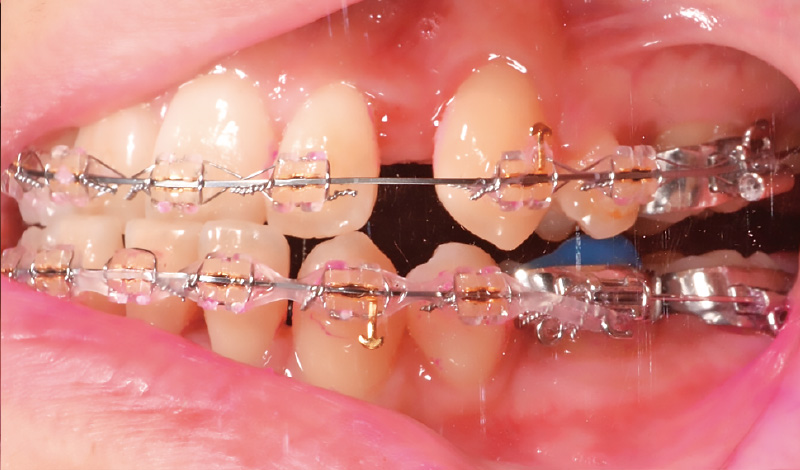

症例2-1 ワイヤー矯正中の10代女性。「ソニッケアー」導入前。プラークの付着量も多く、ブラッシングに苦慮していた。 -

症例2-2 「ソニッケアー」導入後のブラッシング前(正面観)。プラークの付着はブラケット周辺に集中している。 -

症例2-3 同側面観 -